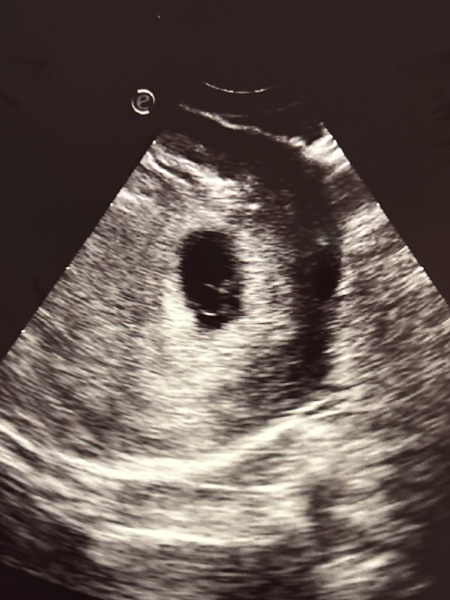

Ultrasound at 5w6days twins?

New here! Had a viability scanning at what I thought was 7 weeks, but adjust 5w 6 days.

Anyways, they looked interested in my ultrasound ( I have a small guess it’s twins). Curious if anyone else had a similar ultrasound and what the results were.

If it was twins I would of expected they would of told you. My twins were seen at my viability scan